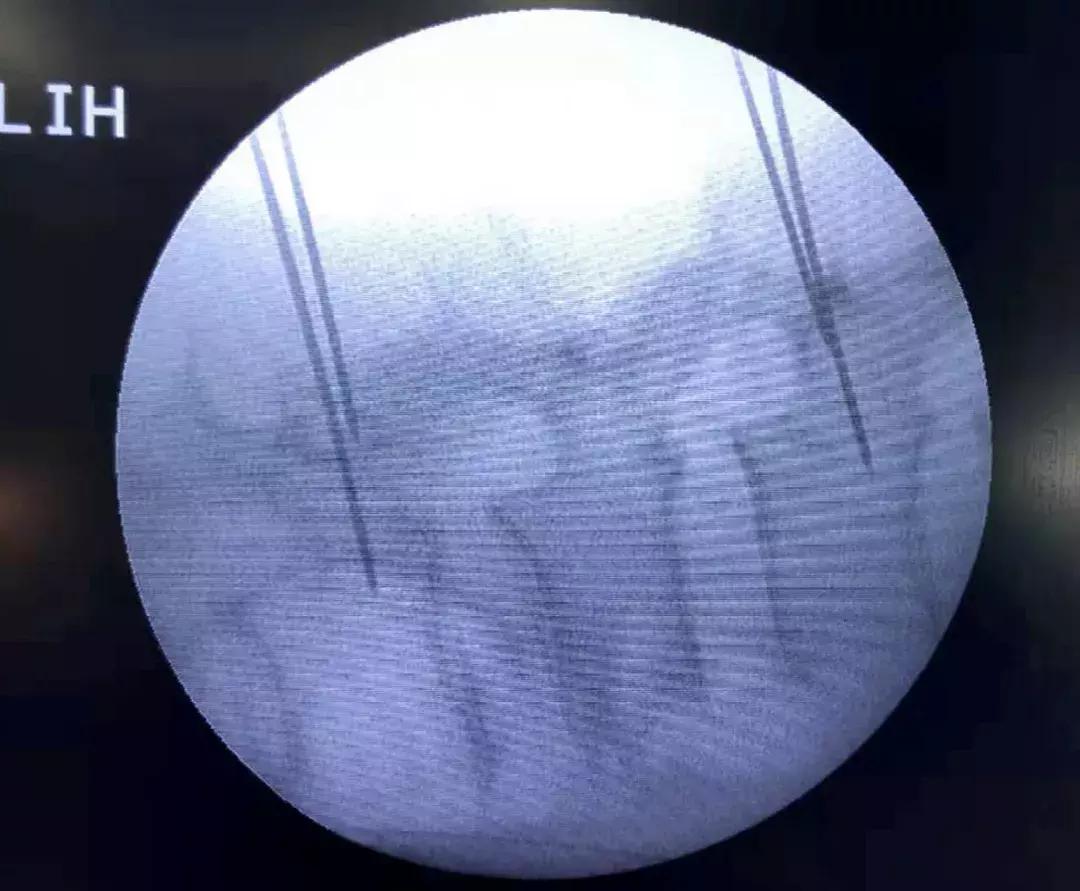

侧位示导针位于椎弓根中心

正位示导针位于椎弓根投影中心